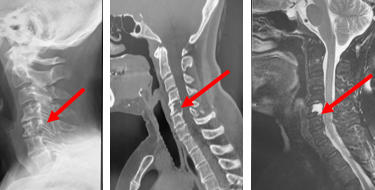

頚椎症性脊髄症・神経根症・頚椎椎間板ヘルニア

どんな病気?

せぼね(脊椎)は7個の頚椎、12個の胸椎、5個の腰椎と仙椎から構成されます。腰椎は主に5つの骨と、間にあるクッションのような椎間板、また神経組織が通っている脊柱管から成り立っています。頚部の神経組織は、脊髄と枝分かれする神経根から構成されています。頚椎症性脊髄症は、骨の変形や椎間板の膨隆、あるいは不安定性などにより、頚椎の脊柱管の狭小化が生じることで頚髄が圧迫される病気です。脊柱管が比較的狭い日本人は欧米人に比べて発症しやすい特徴があります。また、頚椎症性神経根症は椎間板の膨隆や骨棘(骨のトゲ)によって神経根が圧迫される病気です。

検査方法

せぼねの変形や椎間板の傷み具合、すべりや不安定性の有無、脊髄の圧迫の程度、またせぼね全体のバランスなどを見るためにX線検査やCT検査、MRI検査などを行います。進行例では脊柱管の狭さをより詳しく評価するために入院して脊髄造影検査を行う場合があります。どの神経が痛みの原因となっているかを明らかにするため、あるいは除痛目的に神経根に直接麻酔薬を注入する選択的神経根ブロックを行う場合もあります。成人期では血管性のしびれがないか評価するために両手足の血圧を測ったり、骨粗鬆症の有無を評価するために骨密度検査を行うこともあります。

甲状腺がんの第5頚椎転移の症例